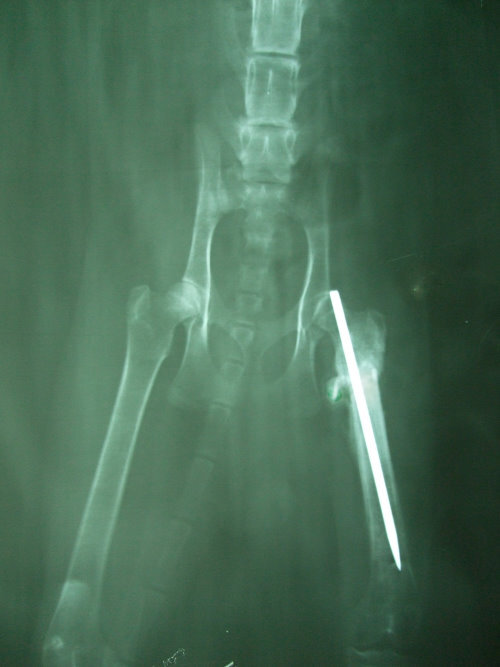

主題: 狗嘴逃生的骨折黑貓 申請者姓名: 蔡葦澄 花色: 申請日期: 2012-07-15 21:07:44 申請者部落格: 申請者臉書網址: 所在縣市/合作醫院: 台北市/澄毅動物醫院 治療費用: 20350元 需求人數: 23人 已結案 (2012-12-01 22:05:16) 報名人員: Anita Wu(已付款)、Jamie(已付款)、Ku-ai Gina Chen(已付款)、Hsin-Yi Chiao(已付款)、蘇圓容(已付款)、艾薇拉(已付款)、viki(已付款)、Claus(已付款)、艾薇拉(已付款)、鳳公主(已付款)、丁小乖(已付款)、無名氏(已付款)、Kent(已付款)、Aaron Liu(已付款)、Minling(已付款)、Ju-jan Hsu(已付款)、sama05(已付款)、陳淑娟(已付款)、上官玉喵(已付款)、不不熊、不不熊(已付款)、kelly(已付款)、Vanna Tai(已付款)、小P(已付款)、 候補人員: 藍琉璃、Evelyn H、小舟、 動物病情說明: 聯合報管理員郭大哥通報,有一隻黑貓被一群浪狗攻擊,叼起來重摔在地,貓躲進大樓垃圾場,平時不方便給外人進出,於是教導郭大哥使用誘捕籠,捕抓後緊急送至動物醫院,X光確認貓咪後腿骨折,手術接回斷骨(氣麻),術後恢復狀況不錯,因為貓咪很兇開籠門會衝撞,所以盡量不去探視驚擾,數日後貓咪開始不吃不喝,瞇瞇眼、淚水量多,似呼吸道疾病,又有輕微脫水,於是上點滴五天後狀況比較穩定,拆點滴投以抗生素治療,因為斷骨需時間復原癒合,住院期間為避免感染貓瘟,於是施打疫苗,貓咪癒後良好,擇日放回。目前仍由郭大哥繼續於原地餵食,健康狀況良好。還請各位能幫忙狗嘴逃生的骨折小黑的醫藥費。